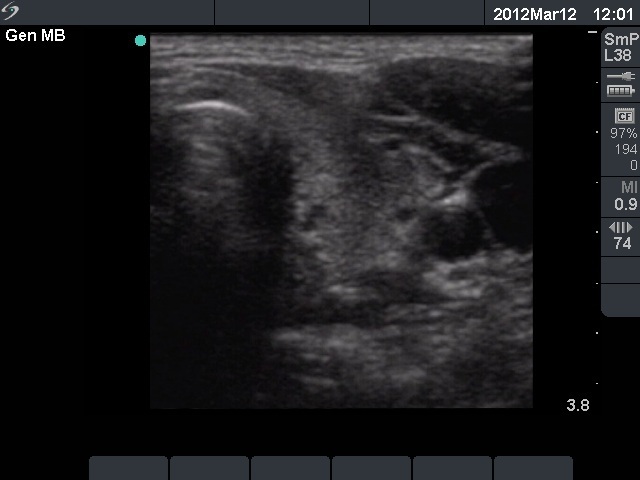

11 months after init. investig. |

7.30 |

0.18 |

4 months after delivery |

Nothing |

71 |

0.24 |

11.9 |

The ultrasound pattern of de Quervain's thyroiditis and that of papillary cancer are very similar: a hypoechogenic lesion with blurred borders are found in both cases. They differ in vascularization statistically but the vascular pattern has only limited practical significance. In the acute phase of de Quervain's thyroiditis the vascularization is generally decreased but even in this case the situation was the opposite. The finding of not one but multiple hypoechogenic areas favored the possibility of subacute thyroiditis.

The relapse of de Quervain's thyroiditis in the contralateral lobe is a very frequent finding but not one year after the appearance of the disease. We supposed that the immunological changes during and after pregnancy explained the relatively late relapse of the disease.